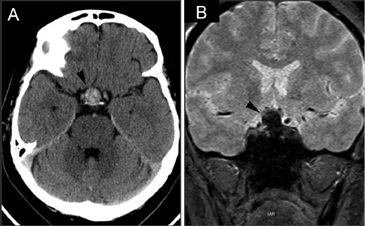

La apoplejía pituitaria (Figuras 21A y 21B) es un síndrome clínico que resulta de una hemorragia aguda o infarto en un tumor pituitario51. En pacientes con macroadenomas no funcionantes la apoplejía es el cuadro de presentación en un 15 a 25% de los casos52. En la minoría de los pacientes con apoplejía se conoce previamente la existencia de un tumor pituitario53. En comparación, la incidencia de apoplejía en pacientes con un tumor pituitario conocido es estimada en menos de 1% por año54. La presencia de sangre en un adenoma pituitario no va siempre acompañada de un cuadro clínico de apoplejía pituitaria y es un hecho frecuente de encontrar (Figuras 22A y 22B); los macroadenomas pueden presentar en el 14% de los casos focos de hiperseñal en TIw en áreas de hemorragia55,56. La evolución temporal de la hemorragia en RM (Figuras 23A, 23B y 23C) es diferente a la hemorragia del cerebro que se reabsorbe en pocas semanas; en la glándula pituitaria la hiperseñal T1w puede mantenerse por largo tiempo57.

Figura 21A. Corte axial transversal a nivel de la cisterna supraselar. La cisterna esta ocupada por una masa pituitaria espontáneamente hiperdensa compatible con hemorragia reciente (punta de flecha). La paciente se presentó con un cuadro de cefalea intenso, que se interpretó inicialmente como una hemorragia subaracnoidea. B. Corte coronal del mismo paciente, secuencia gradiente se observa la extensión supraselar de un adenoma pituitario con una señal muy hipointensa, por la presencia de sangre (punta de flecha). Esta secuencia es muy sensible para detectar hemorragia, ya que la sangre extravasada produce artefactos de susceptibilidad magnética que aparecen como focos de hiposeñal en la imagen.